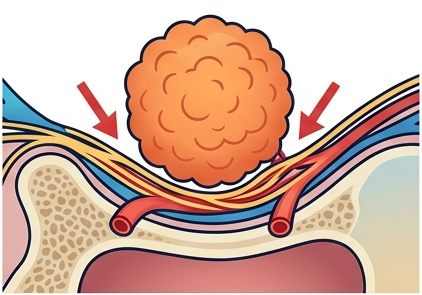

Cancer pain is not a single, uniform experience. It is a complex, shifting composite of multiple pain mechanisms firing simultaneously a tumour pressing on a nerve, an eroded rib, chemotherapy scorching the nerve endings in both hands, radiation fibrosing the lung tissue. Unlike the clean, linear pain of a sports injury, cancer pain evolves, intensifies, and spreads as the disease progresses often faster than oral medications alone can track.

Understanding why cancer hurts is the essential first step to treating it effectively. Cancer pain is not one problem it is a building with six different entry points, each requiring its own specialist key.

In clinical practice, most cancer patients experience mixed-mechanism pain — nociceptive, inflammatory, and neuropathic components simultaneously. This is why a single drug class rarely provides complete relief, and why a multimodal approach combining medications, adjuvants, and targeted interventional procedures is the gold standard.

Cancer pain arises from multiple simultaneous mechanisms: direct tumour compression of nerves and organs; tissue erosion by infiltrating cancer cells; spread to distant organs (bone, liver, lung metastases); damage from chemotherapy (peripheral neuropathy); radiation-induced tissue injury and fibrosis; and pain from surgical removal of infiltrated structures. The severity arises because multiple pain types nociceptive, inflammatory, and neuropathic fire simultaneously, overwhelming simple analgesic approaches.